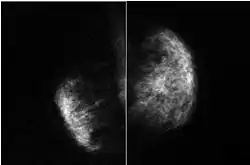

Poland syndrome is sometimes diagnosed at birth, based upon the physical characteristics. Imaging techniques such as a CT scan may reveal the extent to which the muscles are affected.[9] The syndrome varies in severity and as such is often not reported until puberty, when lopsided growth becomes apparent.[10]